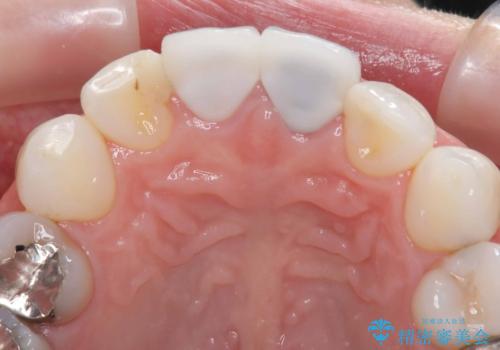

以前他院にてセラミッククラウンを被せていたのですが、セメントの劣化なのか色が青白くなっていました。

歯の形を整えた後、色が透けないよう処置をしてオールセラミッククラウンで治療を行いました。

- 天然歯を削ります